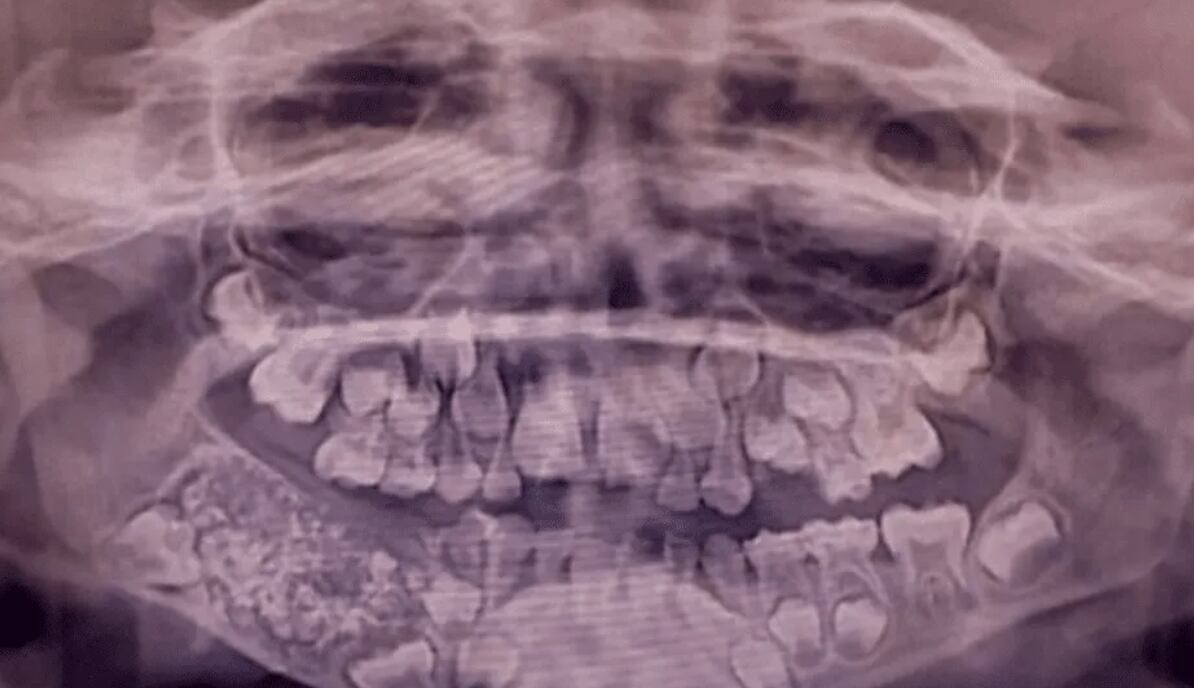

El menor presentaba una hinchazón progresiva en la parte inferior derecha de la mandíbula desde los tres años, pero la falta de cooperación impidió una evaluación inicial efectiva. Al reaparecer los síntomas a los siete años, los especialistas realizaron radiografías y una tomografía que revelaron una “masa en forma de bolsa” con múltiples estructuras duras en su interior.

Durante la intervención, el equipo médico removió esa masa, la cual pesaba aproximadamente 200 gramos. Al abrirla, se encontraron 526 piezas dentales diminutas —entre 0,1 mm y 15 mm— cada una con corona, raíz y capa de esmalte, lo que los médicos compararon con “perlas en una ostra”.